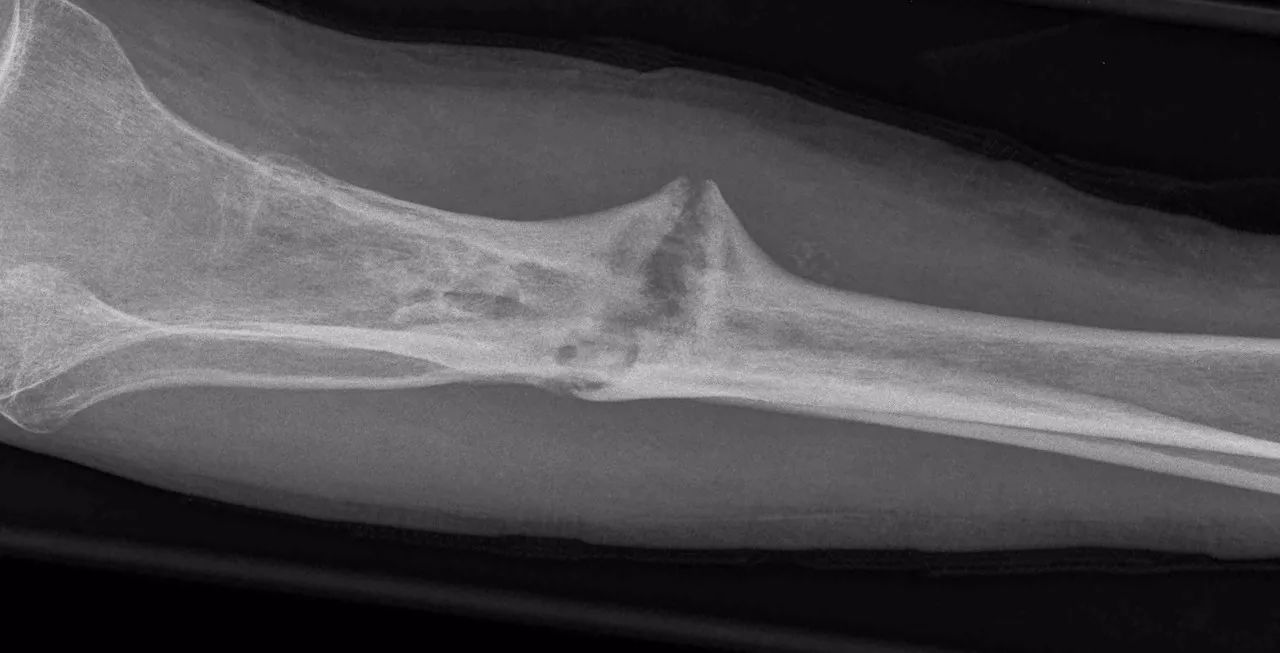

一种典型的骨不连

按照当时的理论,认为骨折处只有紧密接触才能够促进愈合。

可病人的X光照片显示,传统上认为接触才能愈合的骨断端竟然在牵拉的情况下长出了新的骨质。

在牵拉的情况下,缺损区的骨内膜不断产生的骨痂,继而形成致密的骨质。